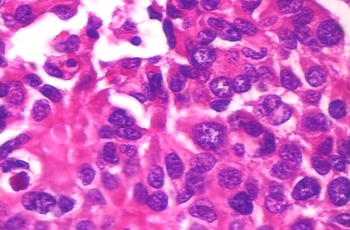

Cancer is a global health problem and can be the greatest barrier to the long life expectancy worldwide in the 21st century [1]. Breast cancer is the most prevalent cancer type among women in 140 out of 184 countries [2]. Its detection usually starts with self-examination and periodic mammography. These exams can identify lumps that will be examined in detail by ultrasound, computed tomography, or magnetic resonance imaging. When some characteristics that can point to a malignant tumor are detected by imaging exams, the final step is the biopsy, which is considered the gold-standard in the diagnosis process because it provides the most accurate diagnosis of the tumor type. The diagnosis procedure should be fast because some malignant tumors grow very fast and have high metastasis probability. Biopsies are a complex diagnosis tool, requiring the acquisition of material (e.g. fine-needle aspiration or open surgical biopsy), tissue treatment (slicing, staining and slide preparation) and analysis by an experienced pathologist. Such an analysis besides being time-consuming, it is subject to inter and intra-observer issues [3]. The variance in the results can be due to the pathologist experience or the hematoxylin and eosin (H&E) staining color differences, which may be related to stain manufacturers, storage age, and temperature.

Computer-aided diagnosis (CAD) systems can help in such an analysis by adding an extra opinion to the pathologist decision. CAD systems can rely on histopathologic images (HIs), which are obtained from tissue slides scanning, to make decisions about tumor characteristics, e.g. benign or malignant [4]. The automatic classification of HIs is a challenging problem in machine learning (ML) because HIs do not have the same structural aspect of macroscopic images such as people’s faces, cars, animals, or traffic signs. One structure that is important in HIs is the nucleus. In images stained with H&E, hematoxylin highlights the nuclei with a blueish color, and eosin highlights the cytoplasm and extracellular matrix in pink. The importance of the nucleus in tumor diagnosis is related to its quantity and format. When a region presents a highly abnormal amount of nuclei, this can be an indication of excessive cell multiplication, meaning a strong sign of a tumor. The format of the nuclei may also represent a signal of a tumor, this is called nucleus pleomorphism. Although blue and pink are the colors expected in H&E stained slides, it is common to face differences in intensity, saturation, and hue in the HIs. When analyzing an HI dataset, it is possible to note the differences in the slides from different patients, when they have been produced using different stain brands or faced variations during the whole process. The pathologist can understand this variation easily due to its expertise in looking at important HI features. However, color variations between patients may introduce a bias to ML algorithms. The image color of a patient’s slide does not vary if the staining process is the same, but the inter-patient slide color, even for the same tumor type, may be different. It is also possible to have images of different patients with similar colors, even if the tumor types are different. Therefore, color normalization may help minimize the color bias. However, color normalization algorithms require a target image as a reference to guide the normalization process [5, 6], which is a complex task that may cause loss of important characteristics. Furthermore, the classification result is closely related to such a reference image.

We present in Fig. 5 an example of HIs of two tumor types with two different magnifications. Figs. 5a and 5b are Ductal Carcinoma images of 40 and 400 magnifications. Figs. 5a and 5b are Adenoma images of 40 and 400 magnification factors. These images highlight the differences in the objective into which the filters are trained. In the 40 magnification, it is difficult to identify nucleus pleomorphism since they are too small. On the other hand, this magnification makes easy to detect forms like the ones that characterize papillary carcinoma. The characteristics of magnifications impact in the network used, taking into account that the small network does not have the capabilities of large objects recognizing, only textures. To the same extent, future work studies may include shallow methods in order to compare the performance of GLPB vis-à-vis other techniques of undersampling and oversampling such as SMOTE and NearMiss algorithms.